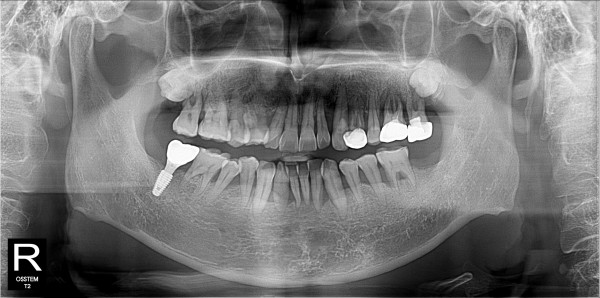

구치부 임플란트 최고관리자 0건 23-11-07 18:30 본문 구치부 임플란트 + 전치부 크라운 목록 이전글구치부 임플란트 23.11.07 다음글구치부 임플란트 23.11.07 댓글목록 0 댓글목록 등록된 댓글이 없습니다.